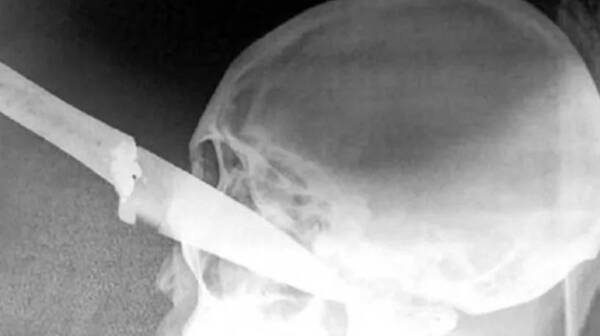

Tras ronda de tragos, ligó un cuchillo en el ojo

Un caso jaryi estremeció ayer a toda la población del barrio Don Bosco de Yby Yaú, ya que un hombre de 65 años terminó con un cuchillo incrustado en uno ...[Leer más]